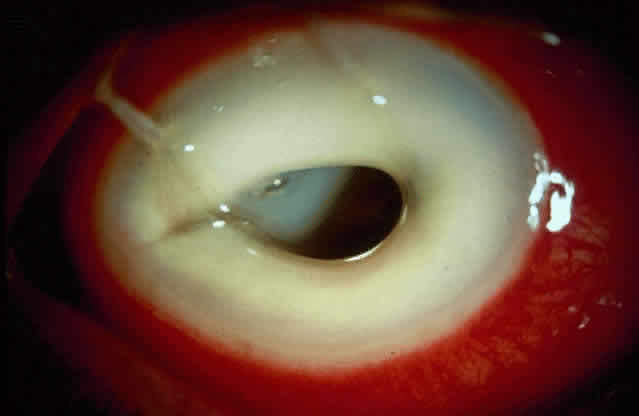

Acanthamoeba infection of the cornea is being reported with increasing frequency. While this is associated with contact lens wear in industrialized countries, in developing countries it is almost exclusively seen in non-contact lens wearers (Fig. 4).6 Misdiagnosis and inappropriate treatment are common.